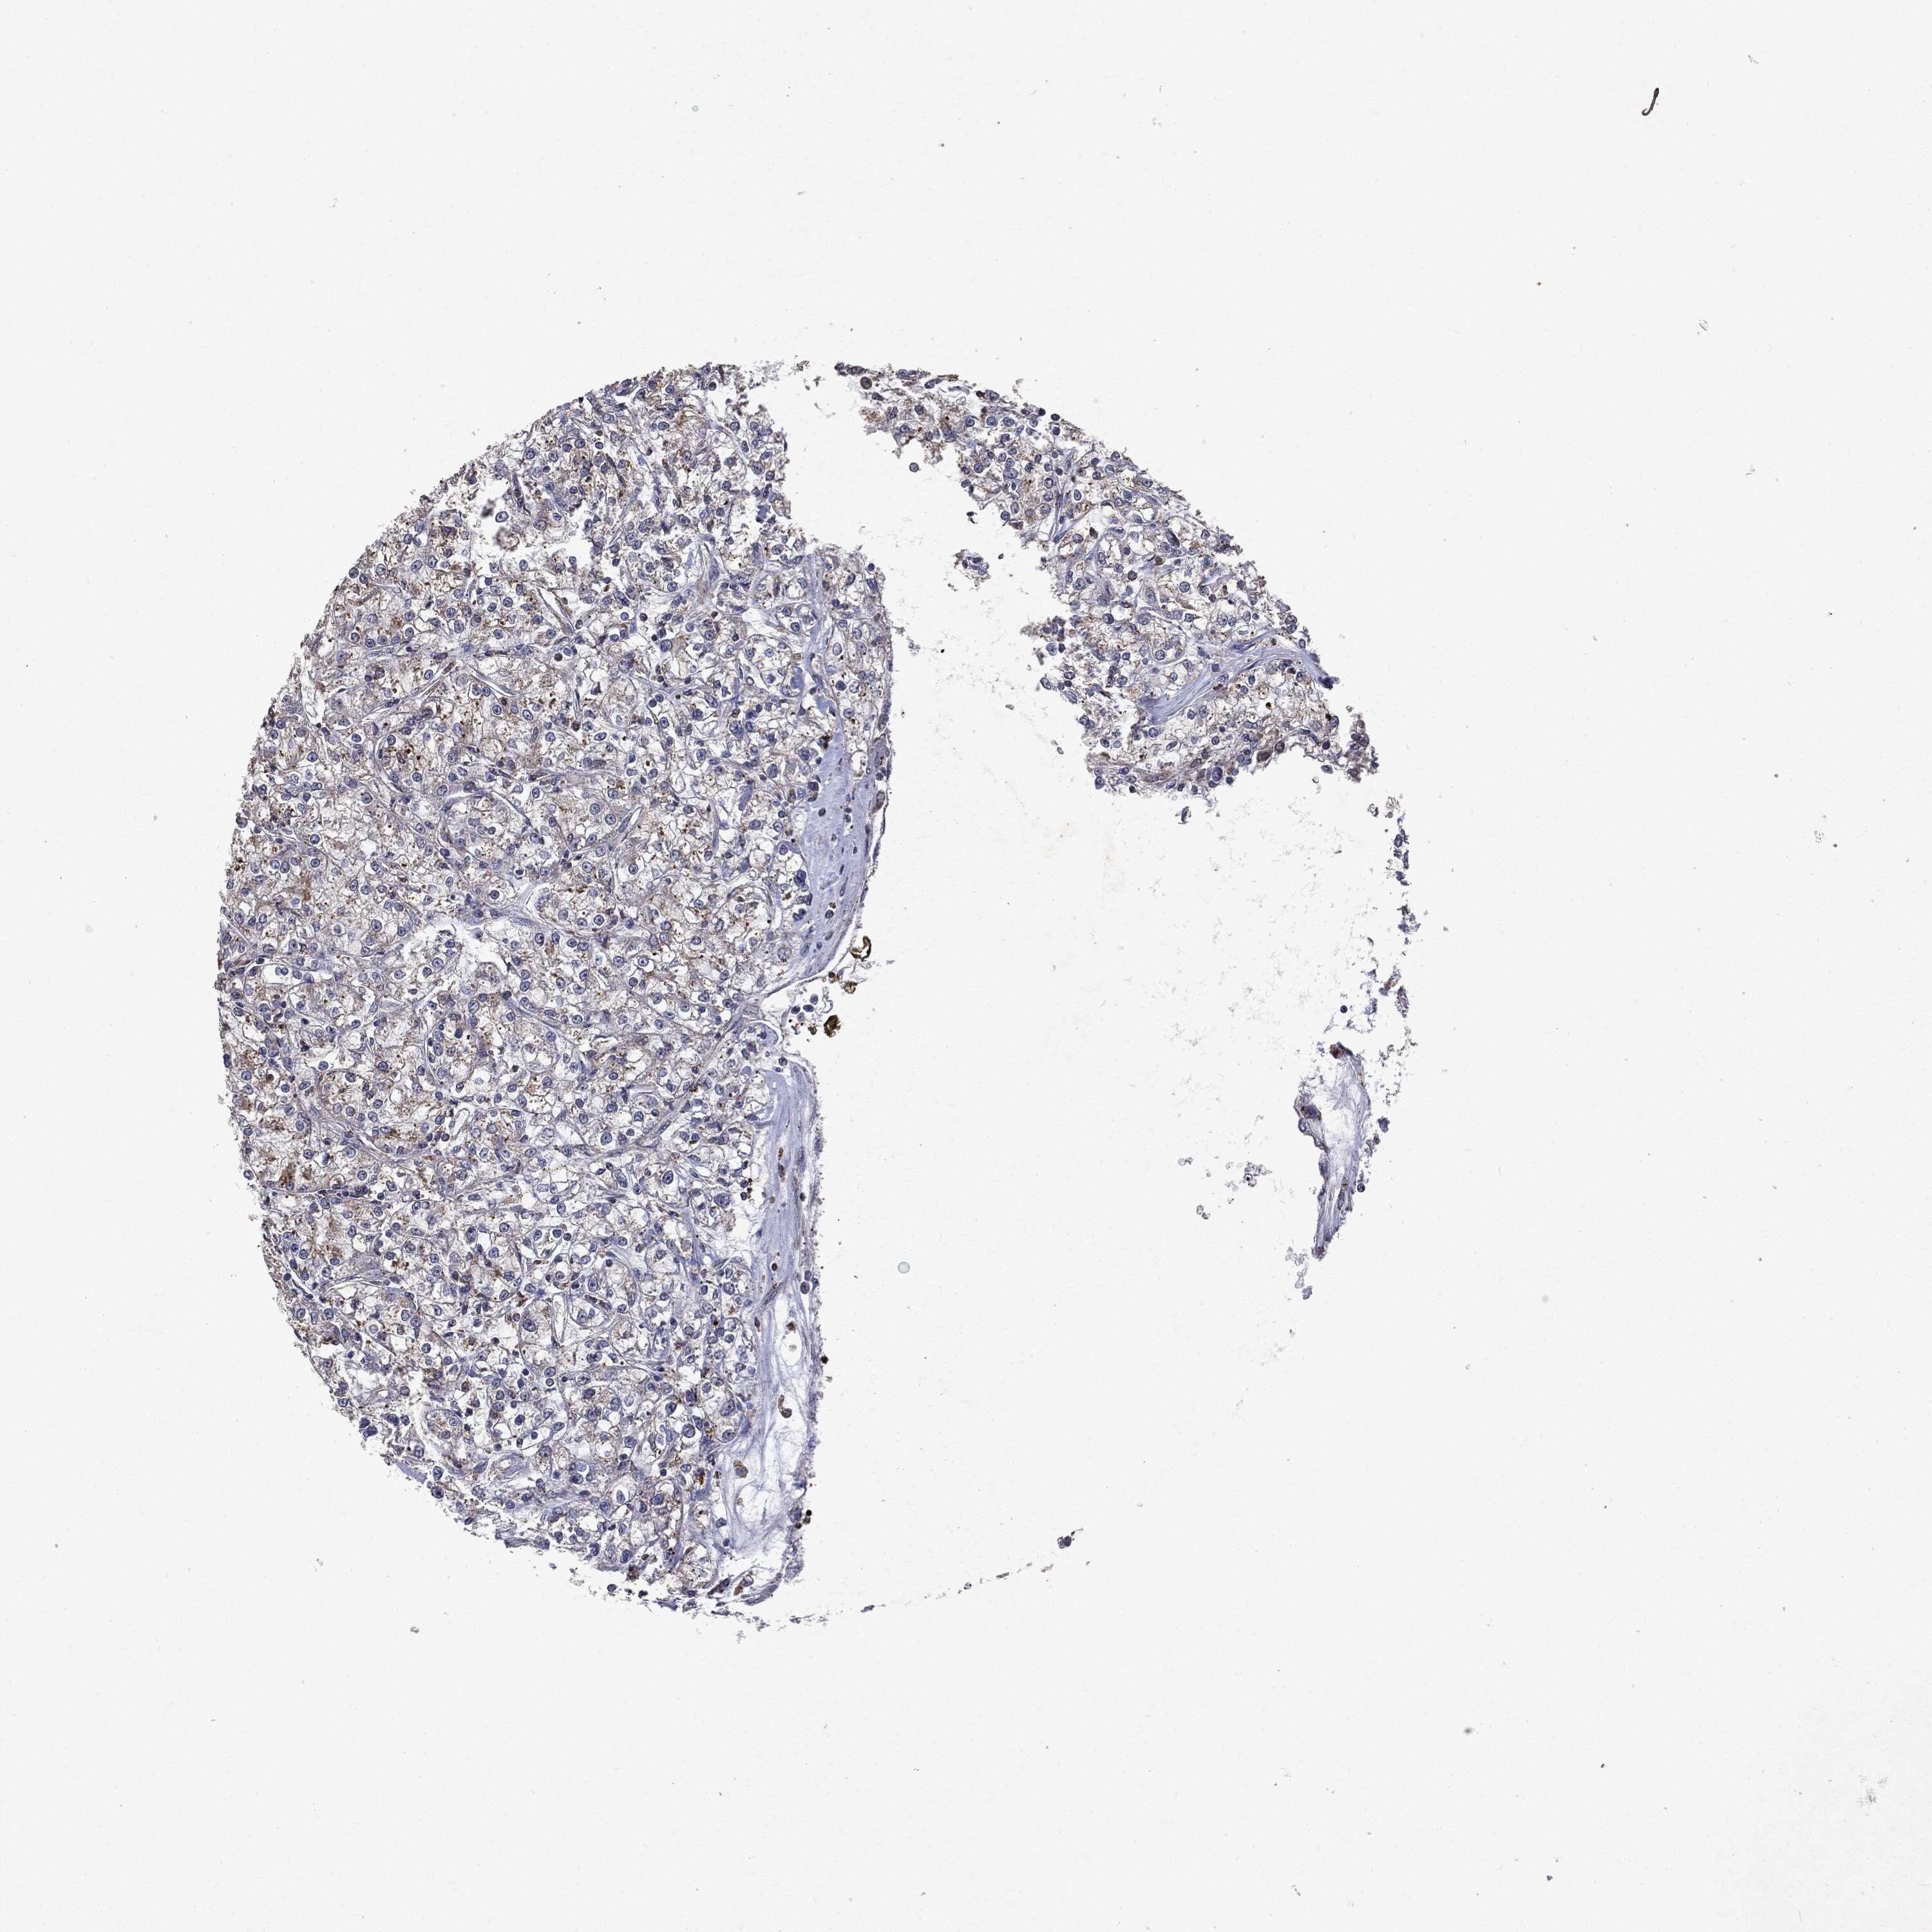

Renal cancer

Kidney renal papillary cell carcinoma